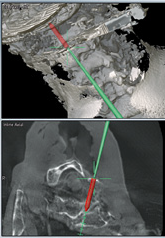

3D Navigation

Multi-modal image registration aims to spatially align medical images from different imaging modalities into the same coordinate space. Image fusion through registration can integrate complementary information from multi-modal imagesto help achieving more accurate diagnosis and treatment.